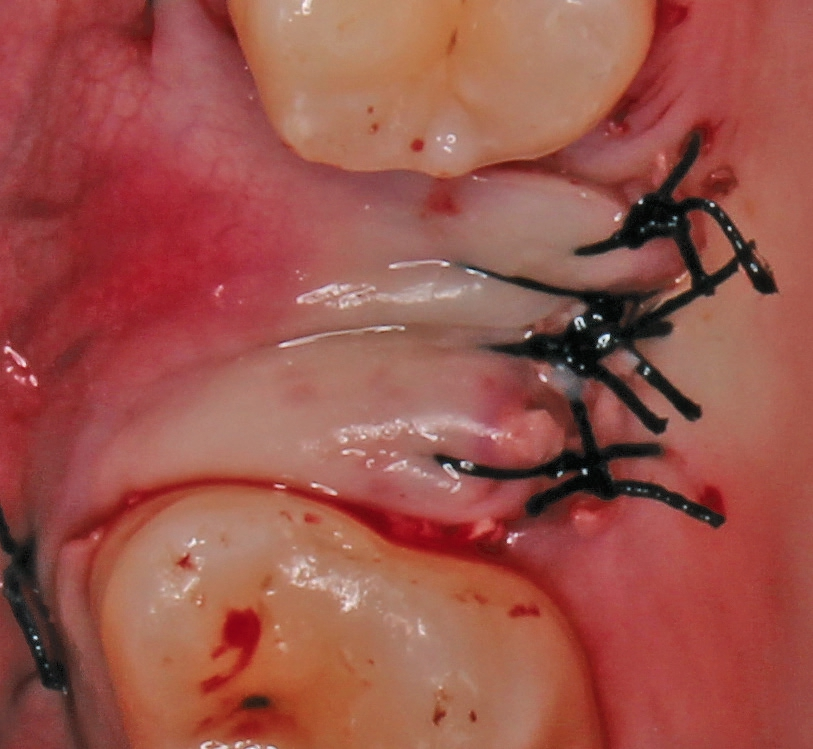

Nach der Präparation des Weichgewebes wurde ein Mukoperiostlappen mit Hilfe der Instrumentenspitze PR2 (Piezosurgery, Mectron, I-Genua) vorsichtig präpariert, um eine suffiziente Deckung der Wunde zu gewährleisten (Abb. 9 und 10). Nach Vorbereitung des Weichgewebes wurde die 3D-gedruckte Bohrschablone auf den Zahnbogen gesetzt und ein Führungsschlüssel mit 2 mm Durchmesser eingesetzt, durch den ein Osteotom einführt wurde, um eine Führung für den nachfolgenden Trepanbohrer in den Knochen kondensierend zu präparieren (Abb. 11). Entlang des Führungskanals wurde das Bett für den allogenen Knochenring (maxgraft bonering; botiss biomaterials GmbH, Berlin) trepaniert (Abb. 12). Der allogene Knochenring wurde extraoral passgenau zugeschnitten und anschließend in die Extrationsalveole platziert (Abb. 13 und 14). Mittels eines breiten Osteotoms wurde der Knochenring samt basalem Knochensegment schablonengestützt nach apikal in den Sinus maxillaris verschoben. Ein parallelwandiges Implantat (Bone Level Roxolid, SLActive, Straumann) mit einem Durchmesser von 4,1 mm und einer Länge von 10 mm wurde zentral in den positionsstabilen Knochenring primärstabil inseriert, mit einer Fixierungkappe (Durchmesser 5,5 mm) versehen und die umliegende Extrationsalveole mit granulärem bovinem Knochenersatzmaterial ausgefüllt (Abb. 15-17). Anschließend wurde die Wunde mit dem Mukoperiostallappen gedeckt und speicheldicht vernäht (Abb. 18). Zur postoperativen Kontrolle wurde ein Orthopantomogramm aufgenommen, auf dem keinerlei Verletzungen benachbarter anatomischer Strukturen zu erkennen sind (Abb. 19). Es folgten zwei radiologische Verlaufskontrollen, vier und sechs Monate nach dem Eingriff, ohne Besonderheiten (Abb. 20 und 21).